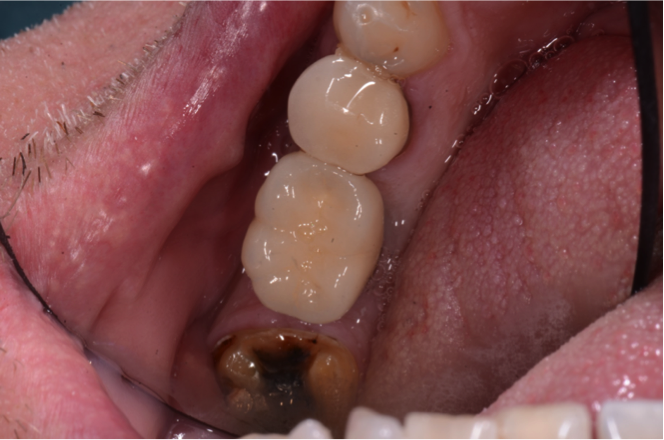

The following case illustrates use of this approach.

The case required placement of a tissue-level implant to restore the patient’s right mandibular first molar. A custom titanium abutment was fabricated with the margins just 0.5 mm above the gingiva to ensure that the area would be free of any retained cement (Figure 23). Figure 24 illustrates how the screw-access hole of the custom abutment was positioned slightly to the buccal. A decision was made to create a PFM crown that would be cemented to the custom abutment. However, the entire restoration would be screw-retained for future retrievability. The PFM that is fabricated for this type of restoration is a very thin coping that does not require a lot of space, is lightweight, and avoids a costly laboratory bill.

Fig 23. Custom titanium abutment in screw-cementable case.

Figure 23

Fig 24. Screw-access hole positioned slightly buccal.

Figure 24